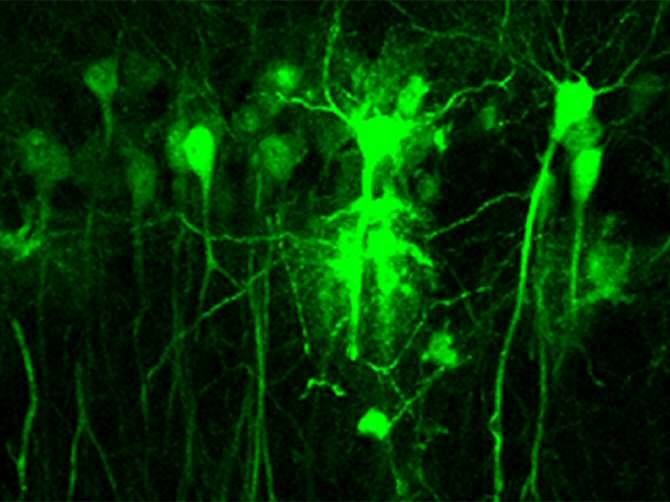

Neuronas hipocampales infectadas con partículas lentivirales que expresan la proteína verde fluorescente para la inactivación del receptor de dopamina D2. (Foto: CSIC)

En la adquisición y la consolidación de la memoria está implicado el hipocampo mediante cambios plásticos en las sinapsis neuronales que almacenan la información recibida de otros núcleos y del exterior. “Hasta el momento se sabía que la dopamina era capaz de modular estos cambios, aunque se desconocían los mecanismos neuronales involucrados. En trabajos previos de laboratorio se había demostrado la importancia del receptor D1 en la memoria espacial y la plasticidad sináptica, pero quedaba por desvelar la implicación del receptor D2”, señala Rosario Moratalla, investigadora del CSIC en el Instituto Cajal.

Combinando el uso de un modelo genético de ausencia del receptor D2 con estrategias de manipulación genética, los investigadores han comprobado que la falta de este receptor reduce la plasticidad sináptica en el hipocampo. (Fuente: CSIC)